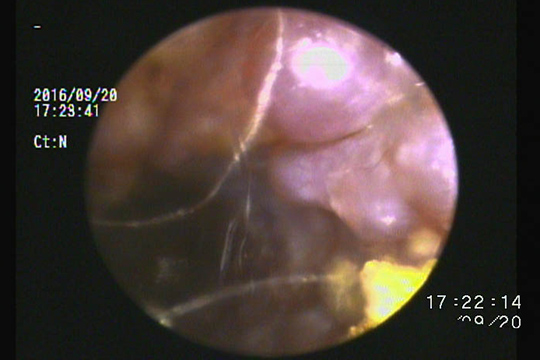

一見綺麗に見えたのですが…鼓膜から水平耳道にかけて毛と耳垢の塊があり、これが痒みの原因になっていました。

このような場合は耳掃除では除去できません。

鉗子を使用して引き出すことが必要です。

綺麗な耳道ですが…鼓膜手前に耳垢が認められます。

不快感がある場合、鉗子による除去が必要です。